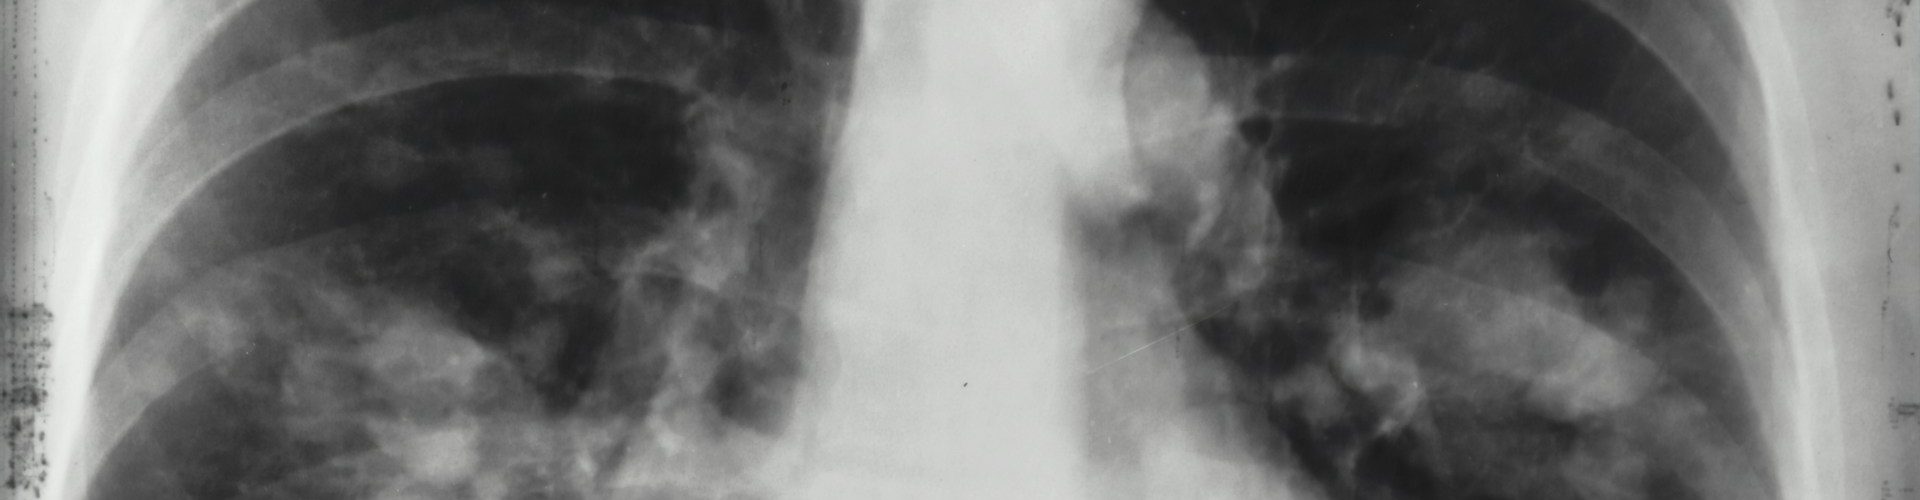

Lung cancer is one of the most frequently diagnosed forms of cancer. Studies have shown that around 12.4% of all global cancer cases are related to lung cancer. If left … Continue reading Home Safety Measures: Tips to Prevent Lung Cancer